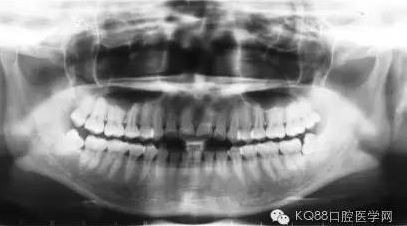

很多人會(huì)有這樣的疑問(wèn),為什么有時(shí)候到醫(yī)院檢查牙齒后醫(yī)生會(huì)建議我們做牙周刮治?為什么做完常規(guī)的潔牙(洗牙)后,還需要進(jìn)行更深層次的牙周刮治呢?

對(duì)大多數(shù)的人來(lái)說(shuō),去醫(yī)院潔牙時(shí),牙齒上的牙菌斑基本上已發(fā)展成為了牙結(jié)石。牙結(jié)石最容易沉積的部位就是下前牙的舌側(cè)和上后牙的頰側(cè)。

牙結(jié)石首先在牙齒與牙齦的交界處沉積,如果堆積的牙結(jié)石沒(méi)有及時(shí)去除,面積會(huì)越來(lái)越大,并朝著牙齦下發(fā)展,導(dǎo)致牙齦炎癥。牙齦炎癥會(huì)引起牙齦腫痛,這種腫痛感就像皮膚被針刺一樣。

長(zhǎng)時(shí)間的牙結(jié)石堆積最后會(huì)造成牙槽骨吸收和牙周袋形成,牙周袋內(nèi)很容易聚集食物殘?jiān)图?xì)菌。這樣惡化循環(huán),最后的結(jié)果是牙齒松動(dòng)、脫落。

由于不使用牙線(xiàn)、刷牙方式的不正確,或者其他因素(如牙列不齊、口腔內(nèi)有不良修復(fù)體、藥物作用、激素水平的變化)的影響,也許一個(gè)人只有牙齦上的結(jié)石,沒(méi)有牙槽骨吸收的現(xiàn)象,此時(shí)只需常規(guī)的潔牙。

當(dāng)牙齦下存在的牙結(jié)石,或有牙槽骨吸收跡象時(shí),常規(guī)潔牙往往無(wú)法清除牙齦下的結(jié)石,此時(shí)需要進(jìn)行牙周刮治了。

牙槽骨一旦吸收很難再生,所以,牙周刮治的目的是為了防止進(jìn)一步的牙槽骨吸收,牙周袋形成以及牙齦出血。更有利于牙齒的穩(wěn)固和健康。

經(jīng)過(guò)牙周刮治(包括齦下刮治和跟面平整術(shù))的患者,每3到4個(gè)月需要進(jìn)行一次牙周維護(hù),因?yàn)樗麄冄例l下的堆積結(jié)石的幾率比一般人的要高。同時(shí),掌握正確的刷牙方式(每天至少刷兩次),堅(jiān)持使用牙線(xiàn),對(duì)維護(hù)牙周健康也能起到一定的作用。

信息來(lái)源:KQ88口腔醫(yī)學(xué)網(wǎng)